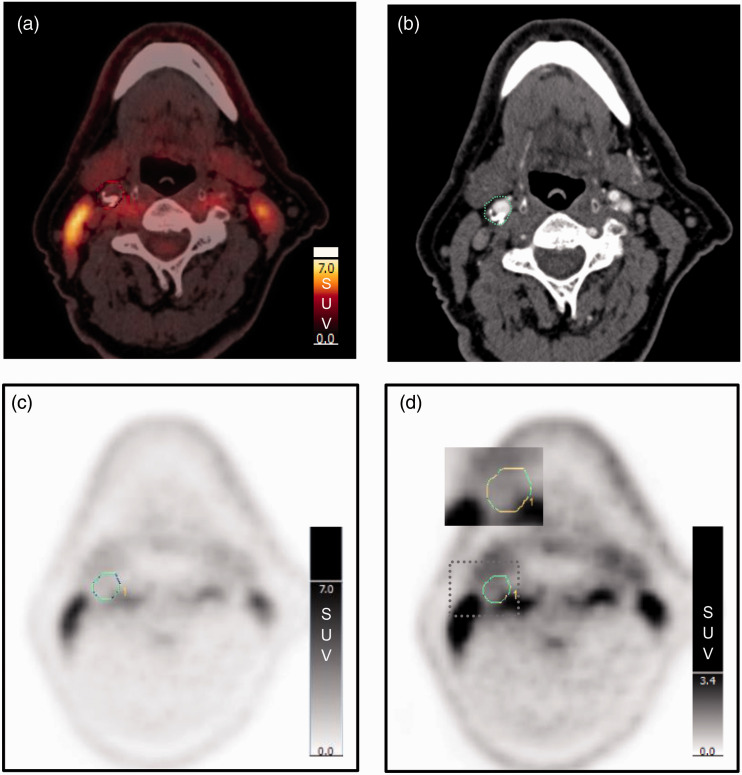

Methods: We assessed the inter-reader variability of different methods for quantification of 18F-FDG uptake in 43 patients with carotid artery stenosis ≥70%. Two independent readers delineated the plaque and collected maximum standardized uptake value (SUVmax) from all axial PET slices containing the atherosclerotic plaque.

Results: Uptake values with and without background correction were calculated and intraclass correlation coefficients were highest for uncorrected uptake values (0.97-0.98) followed by those background corrected by subtraction (0.89-0.94) and lowest for those background corrected by division (0.74-0.79).

Conclusion: Quantification methods without background correction have the highest inter-reader agreement for 18F-FDG PET of carotid artery plaque inflammation. The use of the single highest uptake value (max SUVmax) from the plaque will facilitate the method's clinical utility in stroke prevention.